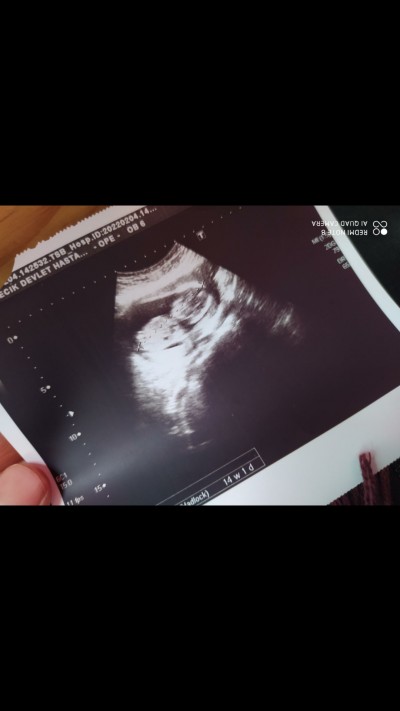

Serklajli

kapalı

hanımlar tahmnde bulunur muusnz

Gebelik haftası

14

Valla hangisi bebeğin kafası, onu bile zor seçtim :) ya kızdır ya oğlan :)